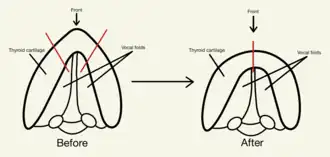

Incision and vocal fold modification

General anesthesia would be administered beforehand. A 5 cm long horizontal incision would then be made at a skin crease above the thyroid notch, allowing the postoperative scar to be hidden under the crease. After flaps have been created under the platysma, the strap muscles would be separated along the midline to expose the thyroid cartilage. This allows a strip of the anterior thyroid cartilage to be removed using electrocautery to effectively reduce the contour of the Adam's apple and the diameter of the laryngeal opening.[18][19]

A quarter of the anterior false folds would also be removed to further reduce the diameter of the upper larynx and to provide a better view of the true vocal folds. Subsequently, up to 50% of the anterior vocal folds is removed and the length of pharynx is shortened to raise the speaking pitch. The overall size of glottal region is also reduced, which diminishes the thyroid notch.[10][19]